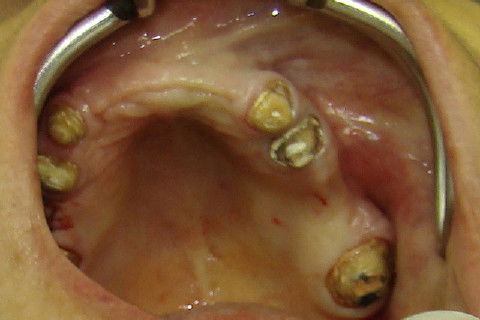

Aspecto clinico da região anterior maxilar, após remoção das proteses antigas

Paciente portadora de reabilitação superior com protese fixa ferulizada e diastemas nos incisivos inferiores, procurou tratamento para "individualizar"os dentes, principalmente os superiores. No planejamento ficou estabelecido que seriam feitos enxertos de elevação do soalho do seio maxilar bilateral e enxertos em bloco na região anterior da maxila. Na mandibula tratamento ortodontico. Após o periodo de cicatrização dos enxertos, implantes foram colocados na maxila. Na mandibula após o termino do tratamento ortodontico, foram colocados implantes. Proteses temporarias foram instaladas e acompanhadas por 6 meses e então feram feitas as reabilitações proteticas superiores e inferiores.